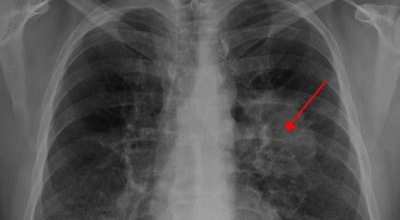

4. 폐암 초기증상 - 가슴 통증

폐암 초기증상으로는 가슴통증이 있습니다. 폐암 환자들의 약 1/3 환자들이 흉통을 호소해요. 흉통이 발생하는 이유로는 폐의 가장자리 부분에 종양이 생기고 그 종양이 암세포를 생성하면서 흉벽과 흉막에 안착해서 통증을 일으키기 때문입니다.

흉통의 경우 여러가지 종류의 이유가 있을 수 있지만 우리가 오늘 다루는 폐암으로 기인해서 생기는 흉통은 계속적으로 쿡쿡 찌르는 느낌의 통증과 가벼운 통증이 아닌 둔탁한 통증을 동반하므로 유의하시길 바랄게요.